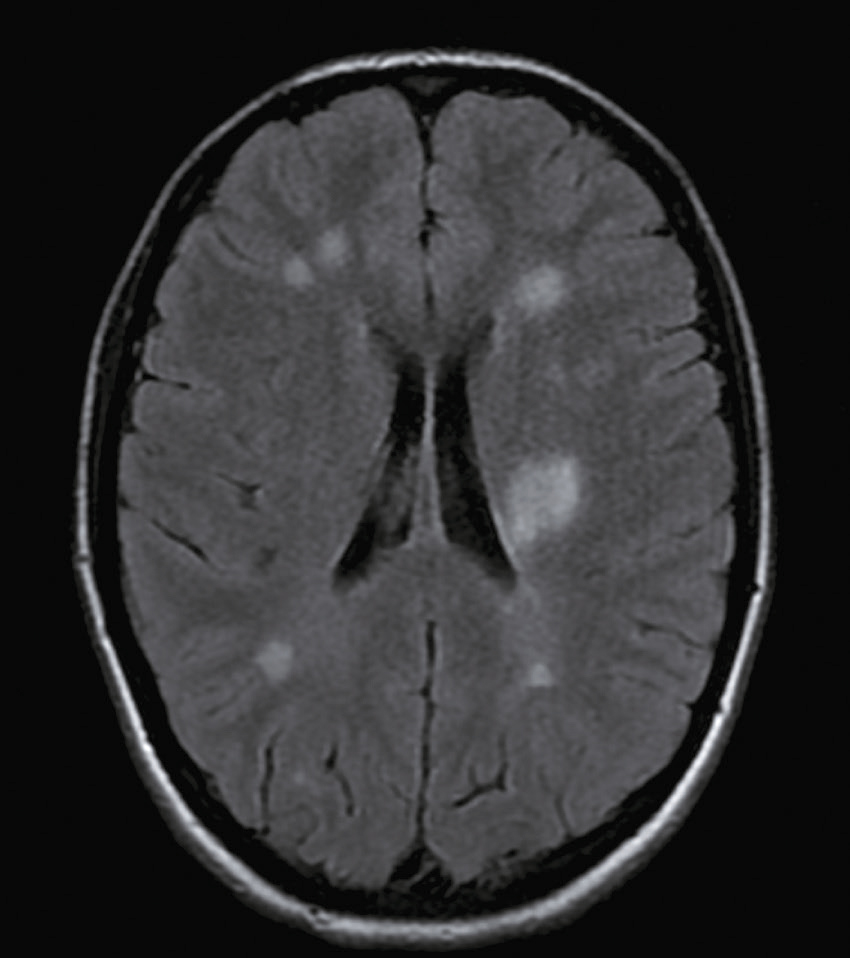

Question 9 – QRM

Une nouvelle IRM cérébrale est réalisée devant cette diplopie. Décrivez le cliché (fig. 31.1).

L'image montre une coupe transversale d'un cerveau humain obtenue par imagerie par résonance magnétique (IRM). Cette image est une vue axiale, ce qui signifie qu'elle est prise horizontalement à travers le cerveau. On peut observer les différentes structures cérébrales, y compris la matière grise et la matière blanche. Les ventricules latéraux, qui sont des cavités remplies de liquide céphalo-rachidien, sont visibles au centre de l'image. Les zones plus claires autour des ventricules peuvent indiquer des anomalies ou des lésions, souvent associées à des conditions neurologiques comme la sclérose en plaques. Les contours du cerveau sont bien définis, et les différentes régions du cortex cérébral sont clairement visibles. Cette image est intéressante car elle permet aux médecins de diagnostiquer et de surveiller diverses maladies neurologiques en visualisant les structures internes du cerveau avec une grande précision. L'IRM est une technique non invasive qui utilise des champs magnétiques et des ondes radio pour produire des images détaillées des organes et des tissus internes, ce qui est crucial pour la détection précoce et le traitement des maladies cérébrales.

- A coupe sagittale

- B séquence T1

- C hypersignaux de la substance blanche périventricu-laire

- D hypersignaux du tronc cérébral

- E hypersignaux juxtacorticaux